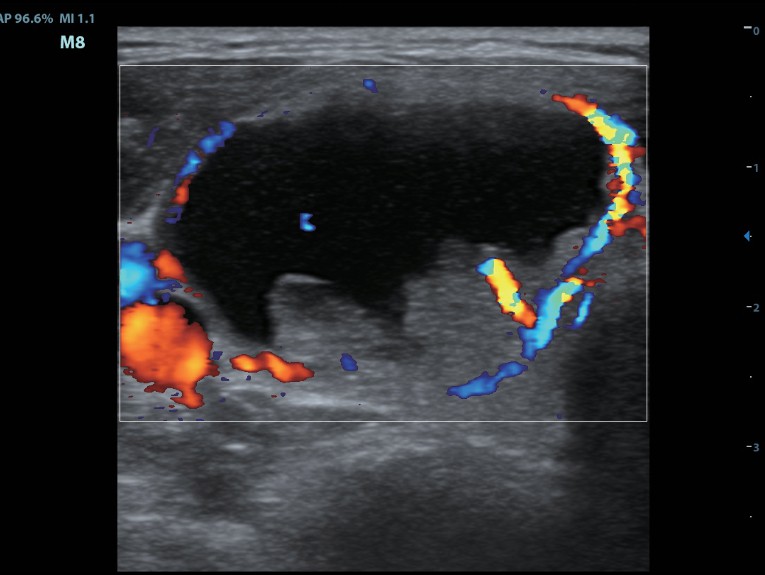

Клинические изображения